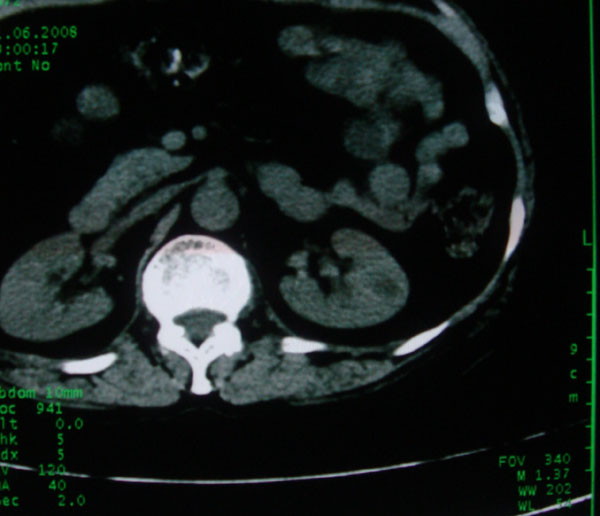

患者女性体查.发现左肾有低密度影,大家考虑是什么.其它方面没有什么异常.低密度影ct值约22hu.

左肾低密度影,境界尚清,查体发现,临床无其他首先考虑肾囊肿,如果增强一下对鉴别有帮助。

左肾不均匀低密度,其形态不规则、边界不清楚,更谈不上锐利。虽无局部凸出,但最后一张片显示仍有比较明显的隆起,我多考虑为肾癌,建议增强或mri检查。